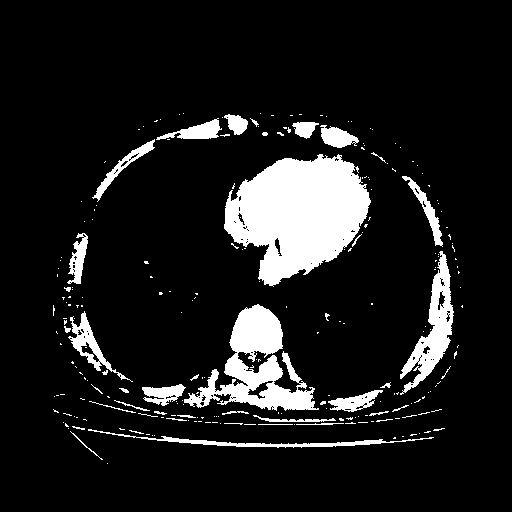

Reconstructed NATIVE CT scan (cycle consistency)

Full window (WL 1023.5, WW 4095 β†’ Low βˆ’1024, High +3071)

Actual HU range: [-1024.0, 3071.0]